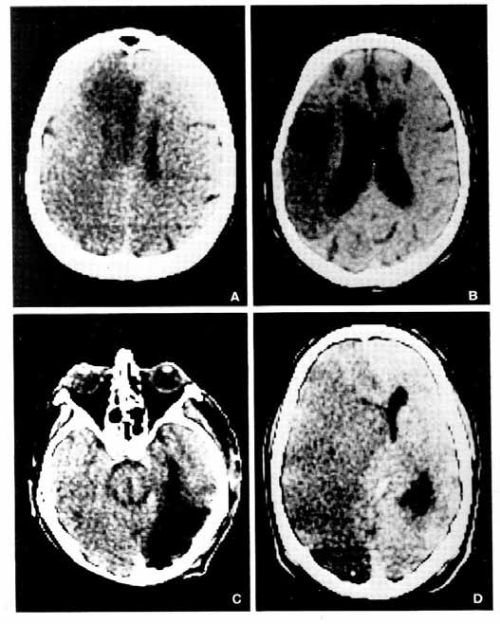

CT nalazi kod infarkta mozga:

1. zbog okluzije prednje cerebralne arterije,

2. srednje cerebralne arterije,

3. zadnje cerebralne arterije.

4. kompletne akutne okluzije unutrašnje karotidne arterije.

Kompjuterizovana tomografija mozga:

1. Senilna demencija Alzheimer-o- vog tipa, sa atrofijom frontalnih lobusa i proširenjem interfemisferične fisure uz simetričnu dilataciju lateralnih moždanih komora,

2. Multiinfarktna demencija bez znakova atrofije mozga, ali sa dve zone ishemične infarkcije u graničnim predelima (water- shed), između prednje i srednje cerebralne arterije, kao i između zadnje i srednje cerebralne arterije,

3. Binswanger-ova subkortikalna arteri- osklerotična encefalopatija sa tipičnim znacima subkortikalne atrofije.